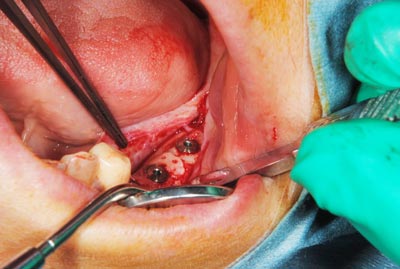

写真は、実際の手術の写真で、丸く採取された骨片が、スクリューで固定されています。

写真は、実際の手術の写真で、丸く採取された骨片が、スクリューで固定されています。

骨の移植手術後、移植した骨片が生着するのを数か月待って、インプラント埋入手術を行いました。写真はその時のもので、移植した骨が周囲の骨と一体化して、しっかりと骨が増えているのが分かります。

骨の移植手術後、移植した骨片が生着するのを数か月待って、インプラント埋入手術を行いました。写真はその時のもので、移植した骨が周囲の骨と一体化して、しっかりと骨が増えているのが分かります。